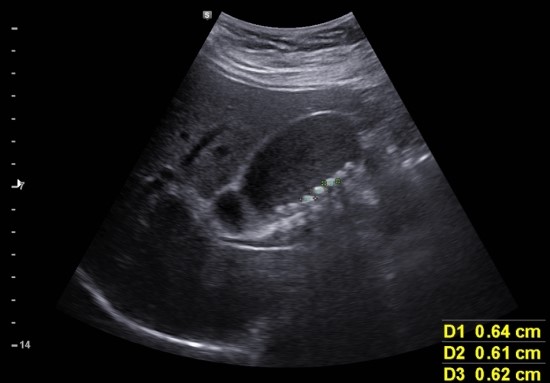

초음파상 크기는 크지 않으나 팽대된 듯한 모양의 담당과 여럿의 담석

담즙 자체도 echogenic한 상태

담낭벽의 비후는 없으며 총담관의 확장은 없음.